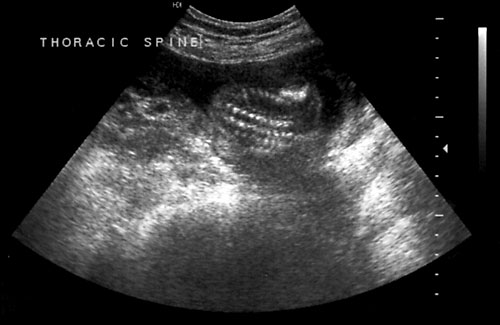

Normal cervical spine at 18 weeks (1). Another normal sagittal view of cervical spine seen in third trimester with folds of fat seen (2). Normal thoracic spine at 18 weeks (3). Normal sagittal view of lumbosacral spine at 18 weeks (4). Normal transverse view of lumbosacral spine at 18 weeks (5). - Extremities (hands/feet)